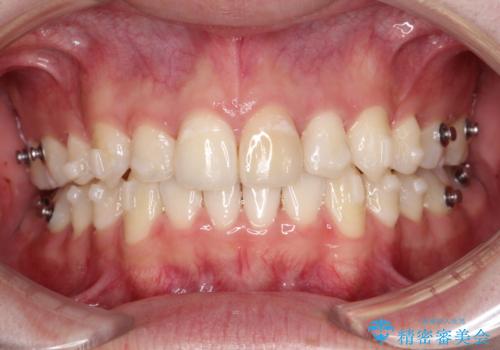

- インビザライン

臼歯の咬合を作るために治療終盤ではゴムかけを行なっています。